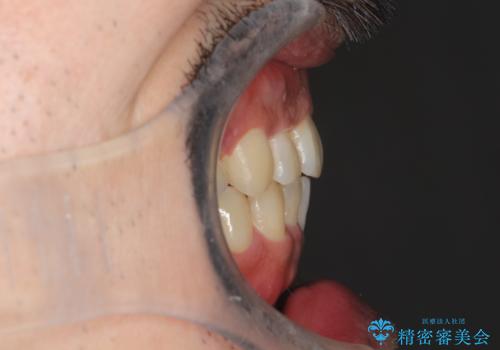

出っ歯の抜歯矯正 裏側ワイヤーによる目立たない矯正

- 出っ歯が気になるとのことで来院されました。

上顎の前から4番目の歯を両側、合計2本抜歯して矯正する計画としました。

目立たない装置がご希望でしたので、上下裏側ワイヤー装置を選択されました。